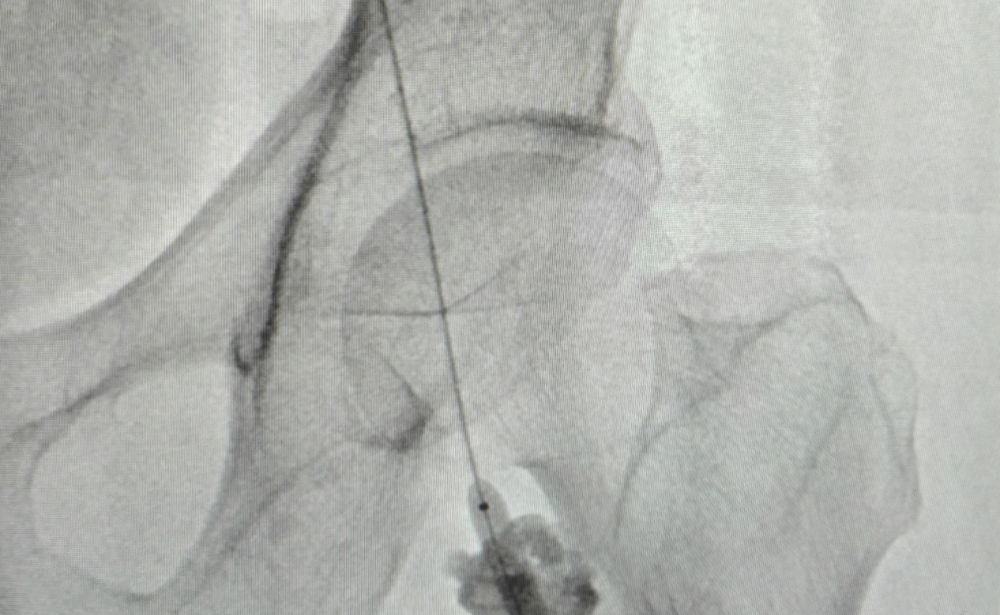

6. PICC Line / Central Line / Permcath / Dialysis Line Placement

The Problem: Patients needing long-term intravenous medication (like chemotherapy or antibiotics), nutrition, or dialysis require secure and reliable vascular access.

Our Solution: Using ultrasound and X-ray guidance, we accurately place various types of central venous catheters with maximum safety and precision.

Patient Benefit: Safer, more comfortable, and reliable access, reducing the need for repeated needle sticks and the risk of complications.